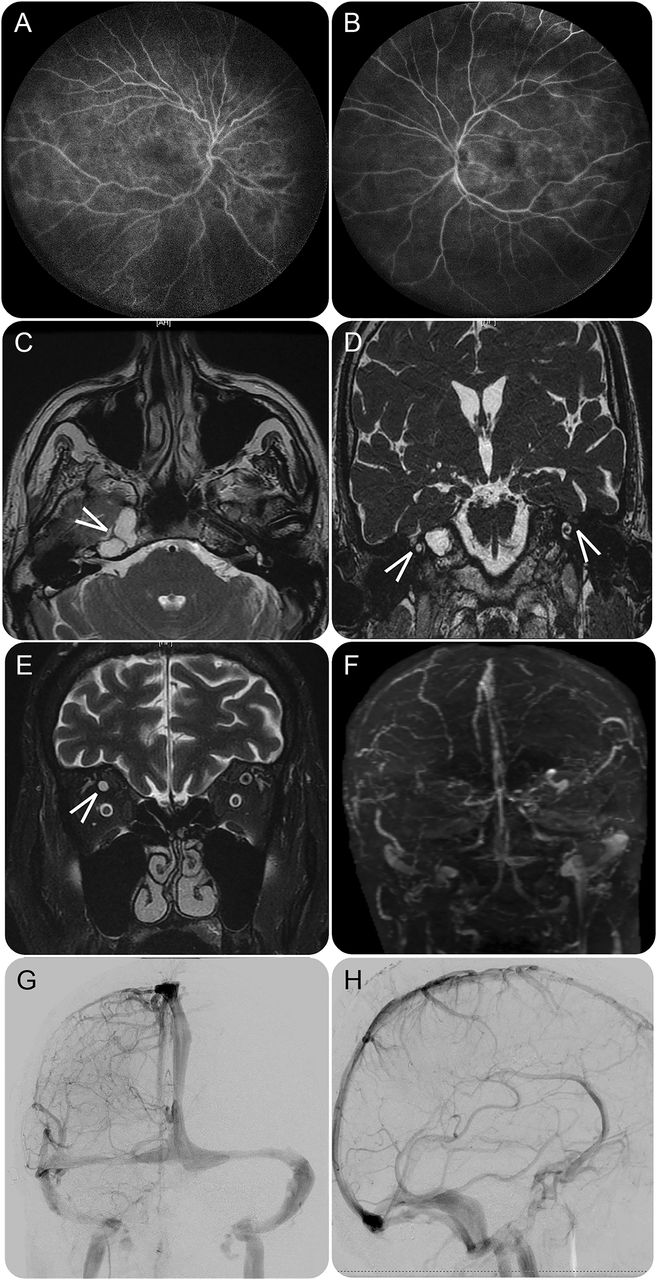

在他的演讲对我们的设施,他在他的双边上肢肌肉力量减弱,左比右。深部腱反射缺席左侧上肢和减少。他的视力是没有光感知双边与固定的瞳孔放大。眼底检查可显示双边视神经盘萎缩与轻度升高利润符合萎缩性视神经乳头水肿和重大视网膜出血与CRVO一致。荧光素血管造影的双眼也暗示CRVO (图中,A和B)。考试也是非凡的右耳的听力损失和严重削弱左耳的听力。听力图显示双边低频SNHL严重,右边比左边。听觉脑干反应是惊人的波形反演的刺激极性的变化,符合双边听觉神经病变。最初的核磁共振成像的大脑是负任何肿块或阻塞性脑积水。核磁共振的内部听觉运河(IACs),然而,对岩石的顶端是重要的脑膜脑膨出、突出到双边IACs (图中,B和C)。国视神经血管严重充血膨胀的perioptic蛛网膜下腔和视神经萎缩双边在MRI中明显的轨道(图E)。磁共振静脉造影照片显示,没有证据表明静脉窦血栓形成或焦点狭窄,尽管所有的静脉窦被广泛地倒塌(图F)。随后,LP与开放进行脑脊液压力45厘米的H2o .脑脊液成分在表的细节e 1上首页®网站首页Neurology.org。脑脊液细菌和真菌的文化,为vasculitides广泛的检查,艾滋病毒抗体也是负的。肌电图和神经传导研究显示多级多神经病的颈神经根病没有证据。

(A和B)荧光素血管造影的眼睛;墙荧光素染色提示中度到重度视网膜中央静脉阻塞。(C)轴向IAC的核磁共振;箭头显示正确的头部形成坚硬的骨头。IAC的(D)冠状核磁共振;箭头显示为两国IACs脑脊髓膜突出的突出。(E)轴向MRI的轨道表明两国高级光学静脉严重充血(箭头)的膨胀perioptic蛛网膜下腔的视神经乳头水肿的说明。(F)磁共振造影术显示弥漫性静脉窦的崩溃。(G和H)静脉术后脑血管痉挛的阶段;正面和侧面视图展示解决扩散静脉崩溃。 IAC = internal auditory canal.

没有明显的临床观察改进后大容量高剂量乙酰唑胺LP和管理。因此,插入ventriculoperitoneal分流。术后脑血管痉挛了,解决分散在静脉静脉崩溃阶段(图中,G和H)。左耳朵的灵敏度提高,也是明显的重复听力图在个月随访。他的视力改善光感知双边解决视神经盘在眼底检查可高度。